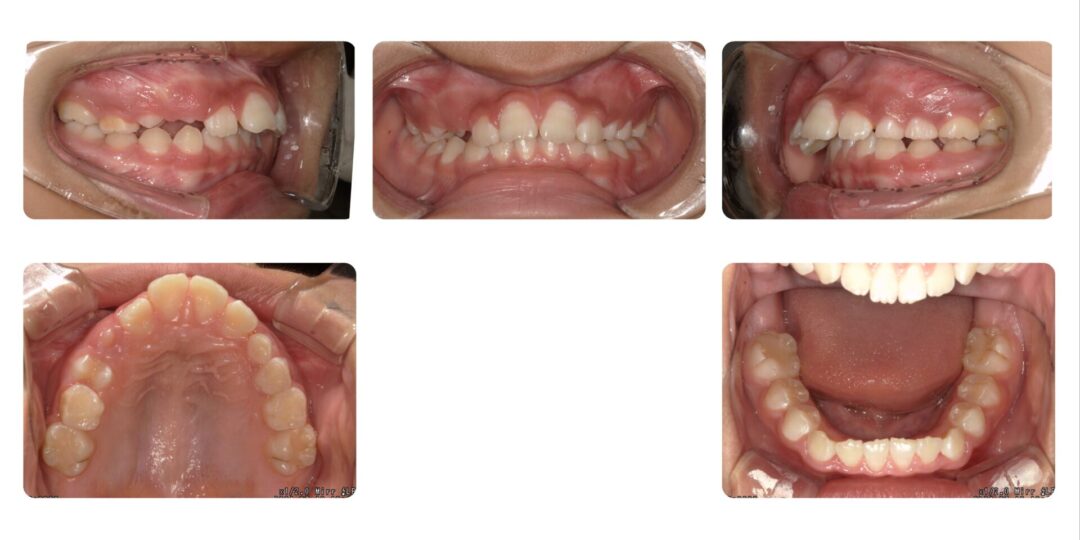

矯正治療後

初診時10歳

第一期治療 拡大ねじ付きバイオネーター

治療期間

1年7か月

治療費用

自由診療 基本料金¥330,000 処置料¥3,300